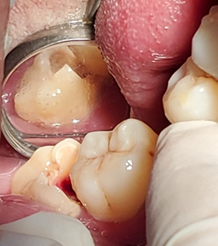

Al interrogatorio paciente refirió antecedente de tratamiento de operatorio en la pieza 4,8 iniciado hace 2 meses atrás y que posterior a un 1 mes se fracturó; el borde afilado de la cúspide mesiolingual tenía la apariencia de una punta de lanza que traumatizaba la lengua (Figura 2). Inicialmente señaló que la cúspide fracturada provocó fricción en la lengua y después de 3 semanas apareció una pequeña úlcera que fue creciendo hasta el tamaño actual.

Al evidenciar la etiología de la lesión, se sugirió como diagnostico úlcera traumática asociada a queratosis friccional, cuya causa fue la cúspide afilada de la pieza 4,8. El tratamiento inmediato fue eliminar la causa, mediante el desgaste selectivo de la cúspide afilada de la pieza 4,8 (Figura 4) y para la úlcera dolorosa fue la aplicación de una solución de ácido tánico 3,75%, pantotenato de calcio 0,75% y lidocaína HCl 1.00% (Bucozone®) tres veces al día por 5 días. También se recomendó una dieta blanda hasta la resolución de la lesión y la desaparición de la sintomatología dolorosa.